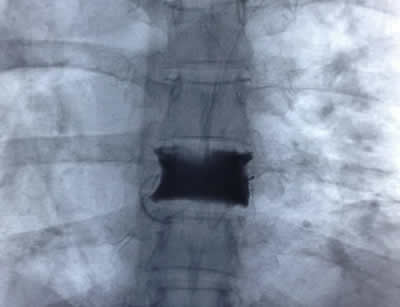

IMÁGENES

Galería de imágenes